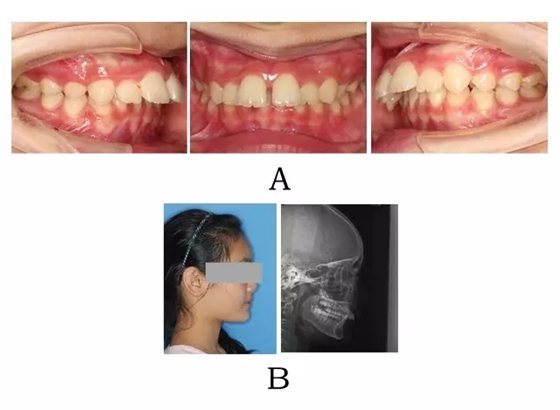

面型前突,唇態(tài)較正常,而下部高度不足、頦唇溝較深,下頜平面較平坦。口內(nèi)表現(xiàn)上頜正?;虬檩p度齒槽性前突,上前牙輕度唇傾。下頜后退,嚴(yán)重的深覆合深覆蓋,磨牙關(guān)系常為遠(yuǎn)中關(guān)系,尖-尖咬合(圖3-1)。

圖3-1:頜位性突面畸形臨床表現(xiàn)及頭顱側(cè)位影像特征。

(A)齒槽與牙列特點(diǎn) (B)側(cè)貌與影像對比

Figure 3-1. Clinical manifestation and cephalometric image for mandibular positional prognathism. (A) Alveolar and dentition specifics. (B) Facial profile and radiographic image.